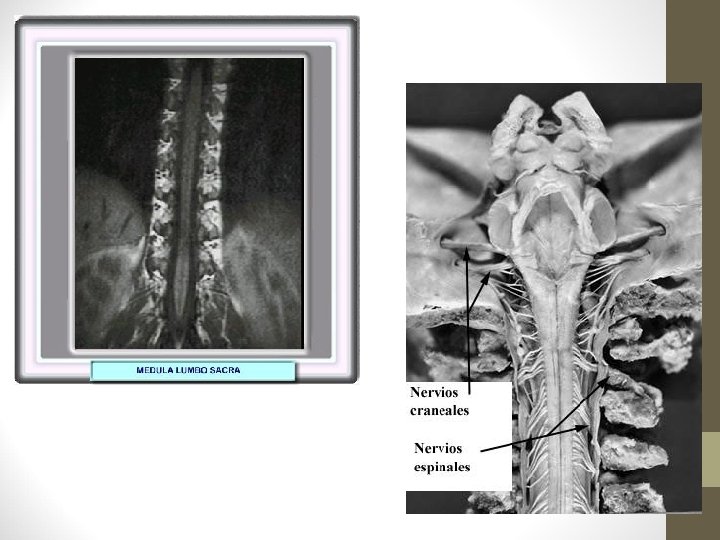

Nervios Raquídeos o Espinales: 31 pares

NERVIOS CRANEALES